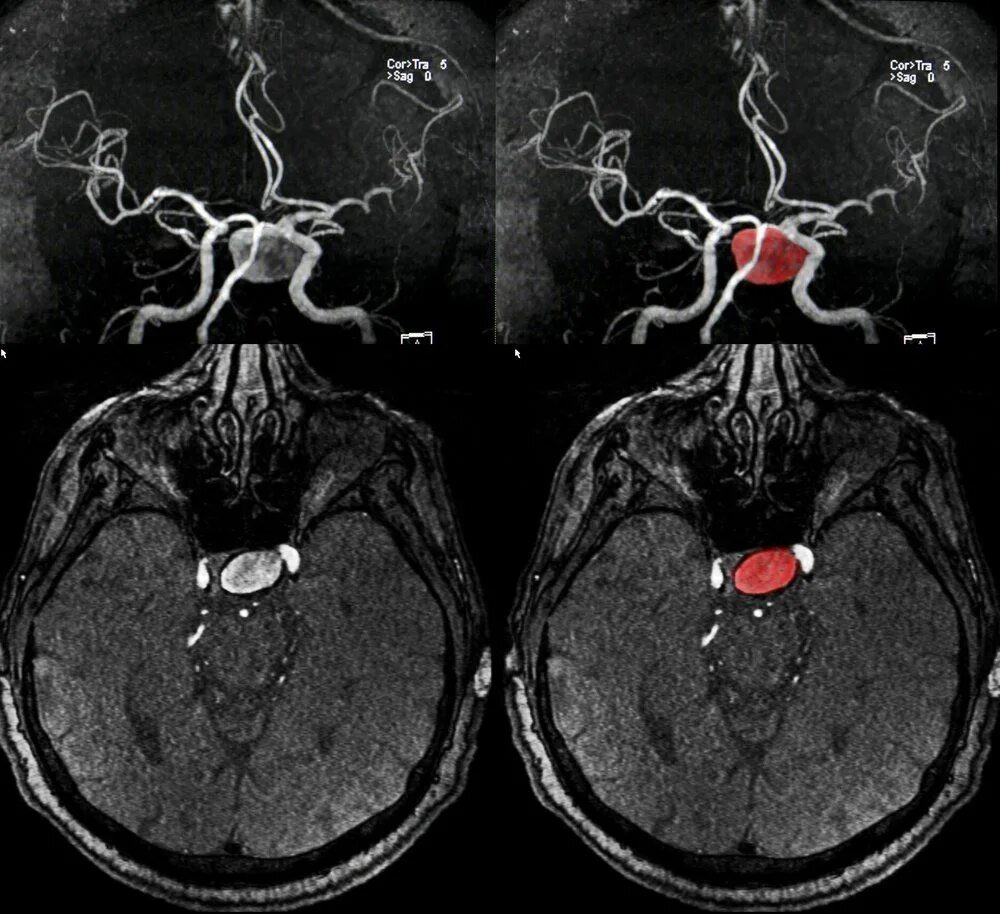

Как проявляется аневризма головного мозга